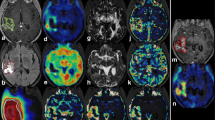

Statistical analysis of 18F-FET PET and DKI. Comparative statistics of diffusion metrics are shown in panels a–c. Compared to treatment-related changes, recurrence presented higher MD, lower rMKT and a decrease in FA. Receiver operating characteristic (ROC) analysis (d and e) demonstrated that TBRmax (AUC ± SE, 0.86 ± 0.05, p < .001) and FA60 (AUC ± SE, 0.86 ± 0.05, p < .001) showed the best performance in univariate analysis, while biparametric assessment of TBRmax + FA60 presented highest diagnostic performance (AUC ± SE, 0.93 ± 0.04, p < .001) with additional diagnostic benefit (difference in AUC ± SE, 0.069 ± 0.034, p = .04). f Correlative evaluation of 18F-FET PET and DKI showed notable correlation of amino acid uptake with FA60 (rs = − 0.46, p < .001) and MD60 (rs = 0.37, p = .004) within the peripheral metabolic compartment. Peripheral metabolic compartments presented slightly increased Spearman’s correlation coefficients. p-value < .05 was considered statistically significant. (*) p-value < .05, (**) p-value < .01, (***) p-value < .001, (ns) non-significant

Quantitative diffusion metrics sampled from the metabolic periphery (see ROI60) presented greater distinction between diagnostic groups (see Table 2 and Fig. 2). Most notably, in the peripheral metabolic region, relapsing glioma presented higher MD (Mdn, 1.40 [IQR, 0.23, n = 39] vs. 1.12 [IQR, 0.29, n = 20], p < 0.001, U = 162), lower rMKT (Mdn, 0.736 [IQR, 0.100, n = 39] vs. 0.844 [IQR, 0.060, n = 20], p < 0.001, U = 153) and decreased FA (Mdn, 0.198 [IQR, 0.081, n = 39] vs. 0.292 [IQR, 0.087, n = 20], p < 0.001, U = 106) than PTRE, as exemplified in Figs. 3 and 4. On the opposite, neuropathologically described (radio-)necrosis (see Fig. 3, panel f and Fig. 4, panel a) demonstrated an inverse signal behaviour with an increase in rMKT and decreased MD. Interestingly, the study comprised a case of a highly proliferative glioblastoma distant to the primary resection site, which presented diffusion restriction and an increase in rMKT, as shown in Fig. 3, panel e. No differences between PTRE with previously treated HGG and LGG (respectively p > 0.05) were observed.

Diffusion characteristics of recurrent glioma. Recurrent HGG typically presented an increase in MD as well as a decrease in rMKT and FA in both metabolic tumour compartments (see a–d). 18F-FET-active lesions are indicated by the white arrow (first row, last column). Magnified insets are shown at the top right. Both metabolic compartments (ROI60, yellow; ROI80, red) are illustrated (the first row, first column). Panel a shows an extensive glioblastoma recurrence (CNS WHO grade 4, IDH-WT, MGMT + , ATRX-) with high 18F-FET uptake (TBRmax, 3.5) and considerable gadolinium-based contrast enhancement. Histopathology revealed an astroglial tumour with mixed radiogenic, reactive and regressive changes. b Recurrent glioblastoma (CNS WHO grade 4, MGMT + , IDH-WT, ATRX-) surrounding the resection cavity. A surrounding rim (see peripheral metabolic compartment) with elevated tracer uptake (TBRmax, 3) and contrast enhancement, which was later shown to correspond to vital tumour cells mixed with radiogenic features and signs of diffuse haemorrhage. Diffusion metrics in this area presented high MD, decreased rMKT and low FA. c Localized 18F-FET uptake (TBRmax, 2.5) corresponding to elevated MD and decreased rMKT that was confirmed to be a recurrent astrocytoma (CNS WHO grade 3, IDH-MT, MGMT-, ATRX + , LOH1p/19q-). In panel d, a small non-enhancing lesion with increased 18F-FET uptake (TBRmax, 2.1) is demonstrated in a patient with multifocal recurrence. Lesion size and 18F-FET uptake might be underestimated in PET due to partial volume effects. Diffusion metrics showed increased MD, low rMKT and FA, suggesting recurrence. Panels e and f exemplify less common clinical presentations of recurrent glioma with low MD and increased rMKT. A recurrent astrocytoma (CNS WHO grade 4, IDH-MT, MGMT + , ATRX + , LOH1p/19q-) distant to the primary resection site (see e) is illustrated with high 18F-FET uptake (TBRmax, 4), low MD and elevated rMKT. Histopathology showed a glial tumour with high proliferation rate in the absence of necrotic features. High cellular (mutant) P-53 accumulation was reported, which is known to have an impact on the expression of various cancer-related genes, suggesting hindered diffusion also as a result of dysregulated protein synthesis. f Recurrent oligodendroglioma (CNS WHO grade 3, LOH1p/19q + , IDH-MT, ATRX-) close to the resection site (not shown in the axial slice) with extensive necrosis and a contrast-enhancing edge with elevated 18F-FET tracer uptake (TBRmax, 2.8). The first biopsy revealed radionecrosis, but a second biopsy 6 months later confirmed recurrence with vital tumour cells, reactive/regressive CNS tissue and necrosis. Although a large fraction of the spherical mass presented elevated rMKT and low MD, diffusion metrics sampled from the metabolically active regions showed inverse signal behaviour with high MD and low rMKT, already suggesting cancer relapse at imaging prior to the first biopsy

Imaging of treatment-related changes. Clinical presentations of histopathologically confirmed PTRE are illustrated. 18F-FET-active lesions are indicated by the white arrow (first row, last column). Magnified insets are shown at the top right. Both metabolic compartments (ROI60, yellow; ROI80, red) are illustrated (the first row, first column). First panel (a) shows a patient with a previously treated anaplastic pleomorphic xanthoastrocytoma (CNS WHO grade 3, LOH1p/19q-, IDH-WT, MGMT-, ATRX-), who presented with a new focal contrast-enhancing lesion with low 18F-FET uptake (TBRmax, 1.7). Following primary resection, the patient received a combined therapy according to the Stupp’s regimen. Upon first relapse, a second-line therapy was started with BRAF/MEK inhibitors and radiotherapy. The new lesion was histopathologically confirmed to be radionecrosis with moderate reactive tissue changes. Diffusion metrics showed increased rMKT and low MD, suggesting microstructural complexity. A patient with a progressive hippocampal lesion (see b) with low 18F-FET tracer uptake (TBRmax, 1.6) is demonstrated, who was previously treated for an oligodendroglioma (CNS WHO grade 3, LOH1p/19q + , IDH-MT, ATRX-) with resection and concomitant radiochemotherapy (CCNU/PCV). Histopathology showed reactive CNS changes without malignancy or active inflammation. Diffusion characteristics were similar to the unaffected contralateral hemisphere indicating low microstructural disarray